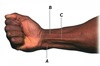

Name the muscles associated with the tendons A, B and C

A - Flexor carpi ulnaris

B - Flexor carpi radialis

C - Palmaris longus